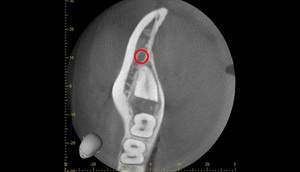

CT画像①

麻布十番歯科での右下の親知らずが真横に生えている症例のCT画像①

CT画像②

麻布十番歯科での右下の親知らずが真横に生えている症例のCT画像②

CTの1部分の画像です。下歯槽神経と親知らずはほんの少し接触しているような状態でした。リスクなど説明し、2回法で抜いていくことにしました。

2回法とは、その名の通り、2回かけて親知らずを抜いていく方法になります。

1回目は歯の頭の部分だけを切るだけになります。2回目は数ヶ月経ってから行いますが、1回目で頭の部分を取ったスペースに歯が伸びてきますので、下歯槽神経と離れたかを確認してから、根の部分を抜いていく、そういった方法になります。

3ヶ月のCT画像①

麻布十番歯科での1回目の親知らず抜歯から3ヶ月後のCT画像①

3ヶ月のCT画像②

麻布十番歯科での1回目の親知らず抜歯から3ヶ月後のCT画像②

1回目から3ヶ月待ちました。下歯槽神経の位置が根の先から離れているのが確認できます。

これで下歯槽神経を損傷させることなく、親知らずの抜歯を行うことができます。